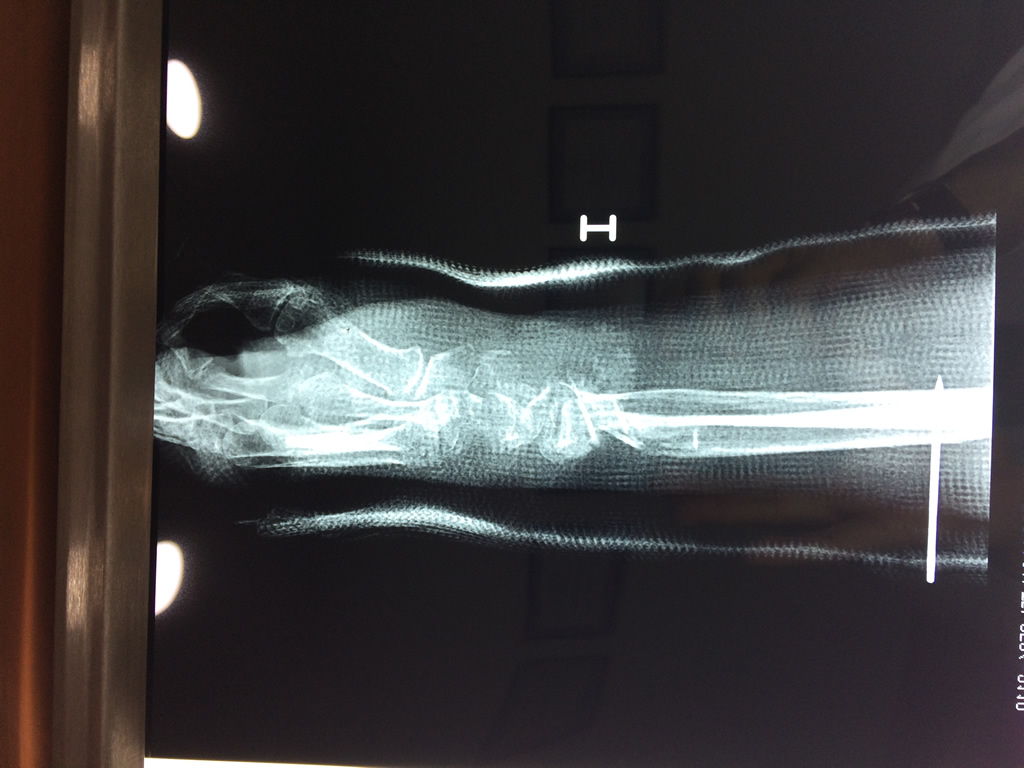

Cirugías de Calcaneo - Cirugías de Muñecas y Manos

Los procedimientos más comunes en cirugía de la mano son aquellos destinados a reparar traumatismos, incluyendo lesiones de tendones, nervios, vasos sanguíneos, y articulaciones; huesos fracturados; y quemaduras, cortes, y otros daños de la piel.